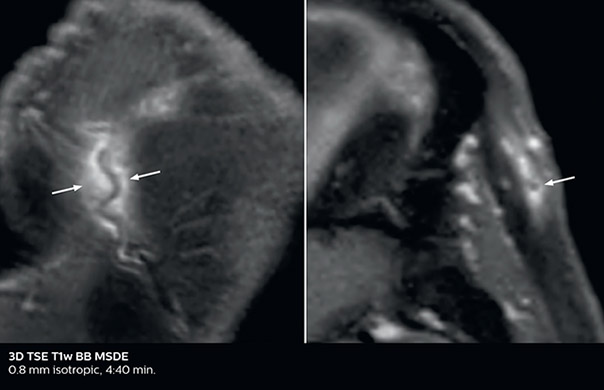

Giant cell arteritis

The 3D TSE T1w black blood MSDE sequence with fat suppression has an isotropic 0.8 mm voxel size and sagittal oblique and axial reformats are made. The images show superficial temporal artery thickening and peri-arterial fat infiltration. The 3D TSE PDw black blood MSDE with fat suppression has 0.55 mm isotropic voxels. The images shows focal involvement of the frontal branch of the superficial temporal artery.

3D TSE T1w BB MSDE

3D TSE PDw BB MSDE